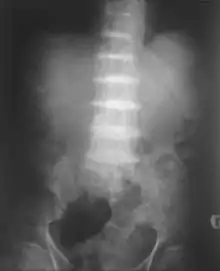

After the age of 30, people begin to develop pain in the weight-bearing joints of the spine, hips, and knees. The pain can be severe to the point that interferes with activities of daily living and may affect ability to work. Joint-replacement surgery (hip and shoulder) is often necessary at a relatively young age.[1] In the longer term, the involvement of the spinal joints leads to reduced movement of the rib cage and can affect breathing.[1] Bone mineral density may be affected, increasing the risk of bone fractures, and rupture of tendons and muscles may occur.[1]